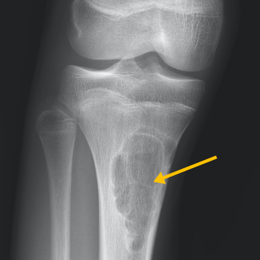

- • Imaging includes X-rays, MRI, CT and PET Scans may also be used as well as bone scans.

Radiographic imaging is used to help form a diagnosis. These include X-Ray, MRI, CT and Bone Scans.

An example of a X-Ray and MRI are shown.